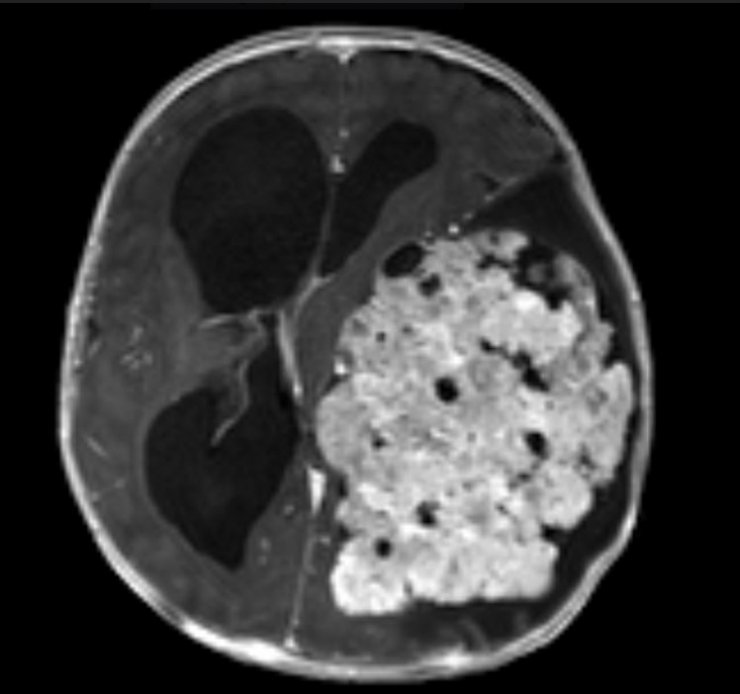

Şanlıurfa'da 1,5 yıllık evli Saniye ve Yunus Kılıç, 3 aylık bebekleri Mehmet Asaf Kılıç'ın kafasının sol tarafında oluşan şişliği fark edince Şanlıurfa Eğitim ve Araştırma Hastanesi'ne başvurdu. Beyninde kitle olduğu belirlenen Asaf bebek, Ankara Sağlık Bilimleri Üniversitesi Gülhane Eğitim ve Araştırma Hastanesi'ne sevk edildi. Asaf'ın çekilen MR'ında beynin sol tarafının tamamen tümör ile kaplı olduğu tespit edildi. Asaf bebeğin ameliyat edilmesi kararlaştırıldı ve 9 saat süren operasyonla beynindeki tümör temizlendi. Asaf bebek, tedavi sürecinin ardından sağlığına kavuştu.

Mehmet Asaf'ın doktoru Beyin ve Sinir Cerrahisi Uzmanı Doç. Dr. Cahit Kural, Asaf'ı ilk gördüklerinde yolunda gitmeyen bir şeyler olduğunu hissetiklerini belirterek, "Acil olarak MR çektirdik. Beyin MR'ında beynin sol tarafını tamamen dolduran, sağ tarafına bası yapan devasa bir kitle vardı. Zaman kaybetmeden hemen ameliyata aldık. Ameliyatta tümörün tamamını çıkardık. Bu büyüklükte tümörler çok nadir görülür. Beynin yarısını dolduran bir tümördü. Hastamız çok küçük, tümör çok büyük, riskli bir ameliyattı. 8-9 saat süren bir ameliyatın ardından iyileşti, sağlıklı şekilde evine gönderiyoruz" dedi.

Çıkarılan örnekleri ileri inceleme için patoloji bölümüne gönderdiklerini belirten Kural, "'Atipik koroid pleksus papillomu" tanısı geldi. Bu çok nadir görülen bir tümör. Beyni bu kadar dolduran tümör görmek, çoğu zaman mümkün değil. Tümörün hepsini çıkardığımız için kemoterapi düşünmüyoruz" diye konuştu.